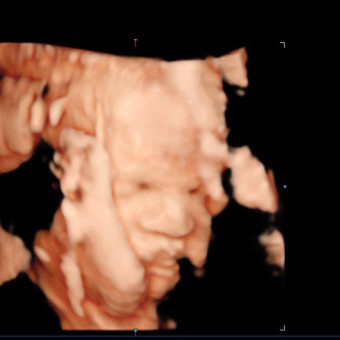

Baby Drew

Guaddy & Drew Manuel

Scottsdale, AZ

February 2026